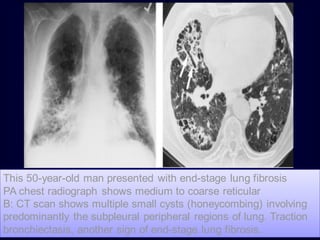

This 50-year-old man presented with end-stage lung fibrosis

PA chest radiograph shows medium to coarse reticular

B: CT scan shows multiple small cysts (honeycombing) involving

predominantly the subpleural peripheral regions of lung. Traction

bronchiectasis, another sign of end-stage lung fibrosis.

b. Reticular Pattern Areticular pattern results from the summation or superimposition of irregular linear opacities. The term reticular is defined as meshed, or in the form of a network. Reticular opacities can be described as fine, medium, or coarse, as the width of the opacities increases. A classic reticular pattern is seen with pulmonary fibrosis, in which multiple curvilinear opacities form small cystic spaces along the pleural margins and lung bases (honeycomb lung)

• 178.

This 50-year-old manpresented with end-stage lung fibrosis PA chest radiograph shows medium to coarse reticular B: CT scan shows multiple small cysts (honeycombing) involving predominantly the subpleural peripheral regions of lung. Traction bronchiectasis, another sign of end-stage lung fibrosis.